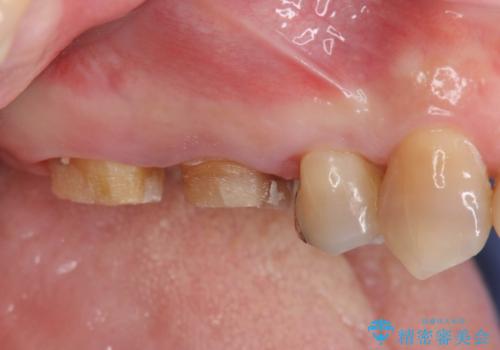

歯周ポケットの除去と再補綴治療

歯周組織検査・X線検査の結果、中等度の歯周病であることがわかりました。

歯周ポケットの除去を歯周外科により行ったのち精度が高く清掃のしやすいセラミック治療による再補綴を行います。